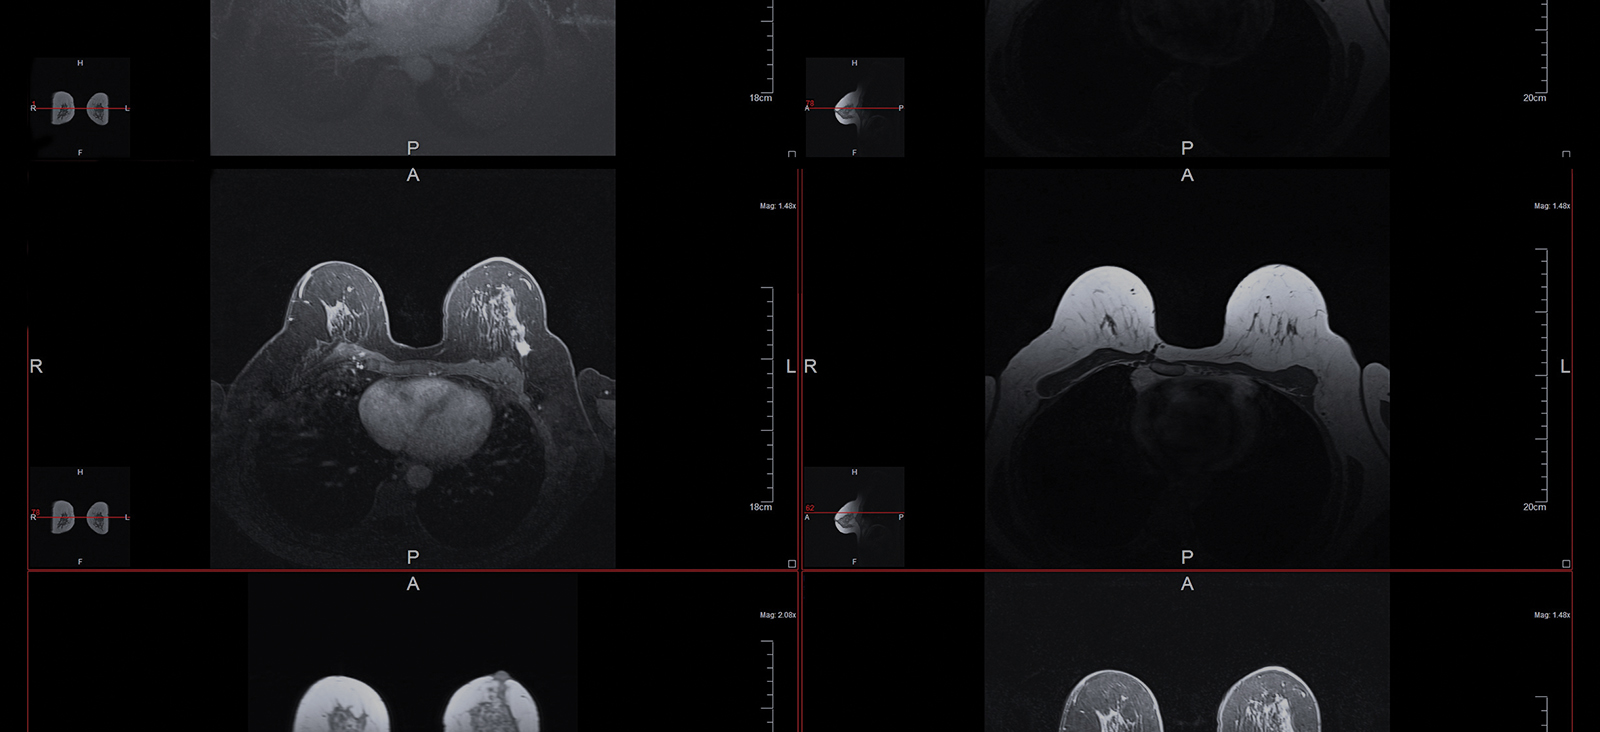

Ushering Breast Cancer Into a New Era of Collaborative Care

As Clinical Director of the Breast Cancer Program at UT Southwestern Harold C. Simmons Comprehensive Cancer Center, Heather McArthur, M.D., M.P.H., is responsible for overseeing clinical care of breast cancer patients within the UT Southwestern Health System. She also specializes in breast cancer research and has pioneered several clinical trials.

Dr. McArthur, who joined Simmons Cancer Center in 2021, is internationally recognized for her research on innovations in the diagnosis and treatment of breast cancer. She has been a principal investigator on various national and international clinical trials and a pioneer in developing novel immunotherapy strategies.